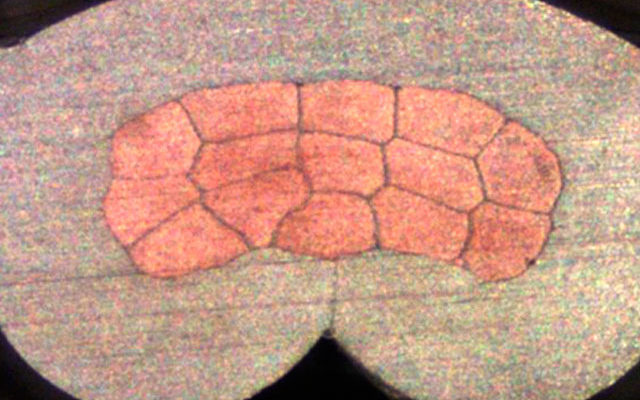

2. Cross-view research